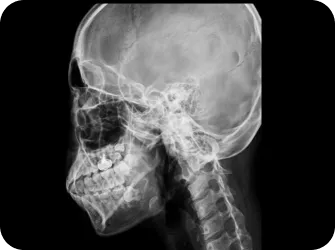

안면 두개골 엑스레이 검사

Submento Vertex View 포함

안면 두개골 CT

경추 1,2번의 변위 파악